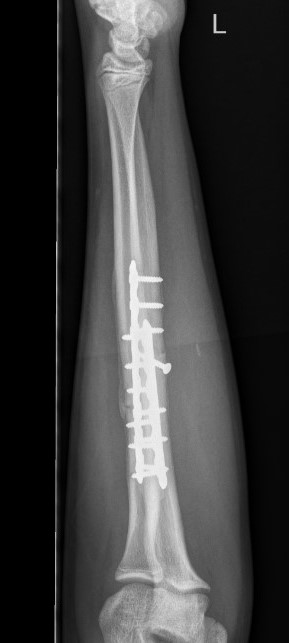

3. Intramedullary elastic nail

Advantage

- smaller scars with insertion

- easier to remove than plates

Disadvantage

- generally immobilized

- must be removed

- non anatomical reduction compared with plates with theoretical risk of loss supination / pronation

- risk of extensor tendon rupture due to prominence of nails at insertion sites

TENS technique

Technique

Radius (typically first as more difficult to reduce)

Entry point with awl 2 cm proximal to distal physis

1. Radial styloid / distal lateral entry

- ensure radial nerve / cephalic vein, 1st extensor compartment protected

2. Listers tubercle / dorsal entry

Elastic Nail size

60 - 70% of the intramedullary canal

Typically 1.5 - 2.5 mm

Fracture reduction

Avoid passing nails incorrectly multiple times as may cause compartment syndrome

Bend tip of elastic nail

May need small open reduction

Cut nail

Withdraw 1 cm, cut with endcutter, then advance

Ulna (usually reduced after radius fixation)

Entry point 2 cm distal to apophyseal plate

1. Proximal lateral

- avoids ulna nerve

3. Distal medial

Postoperative

Cast in supination to tighten interosseous membrane

Cast 6 weeks

Removal of TENS at 4 - 6 months once osseous union established